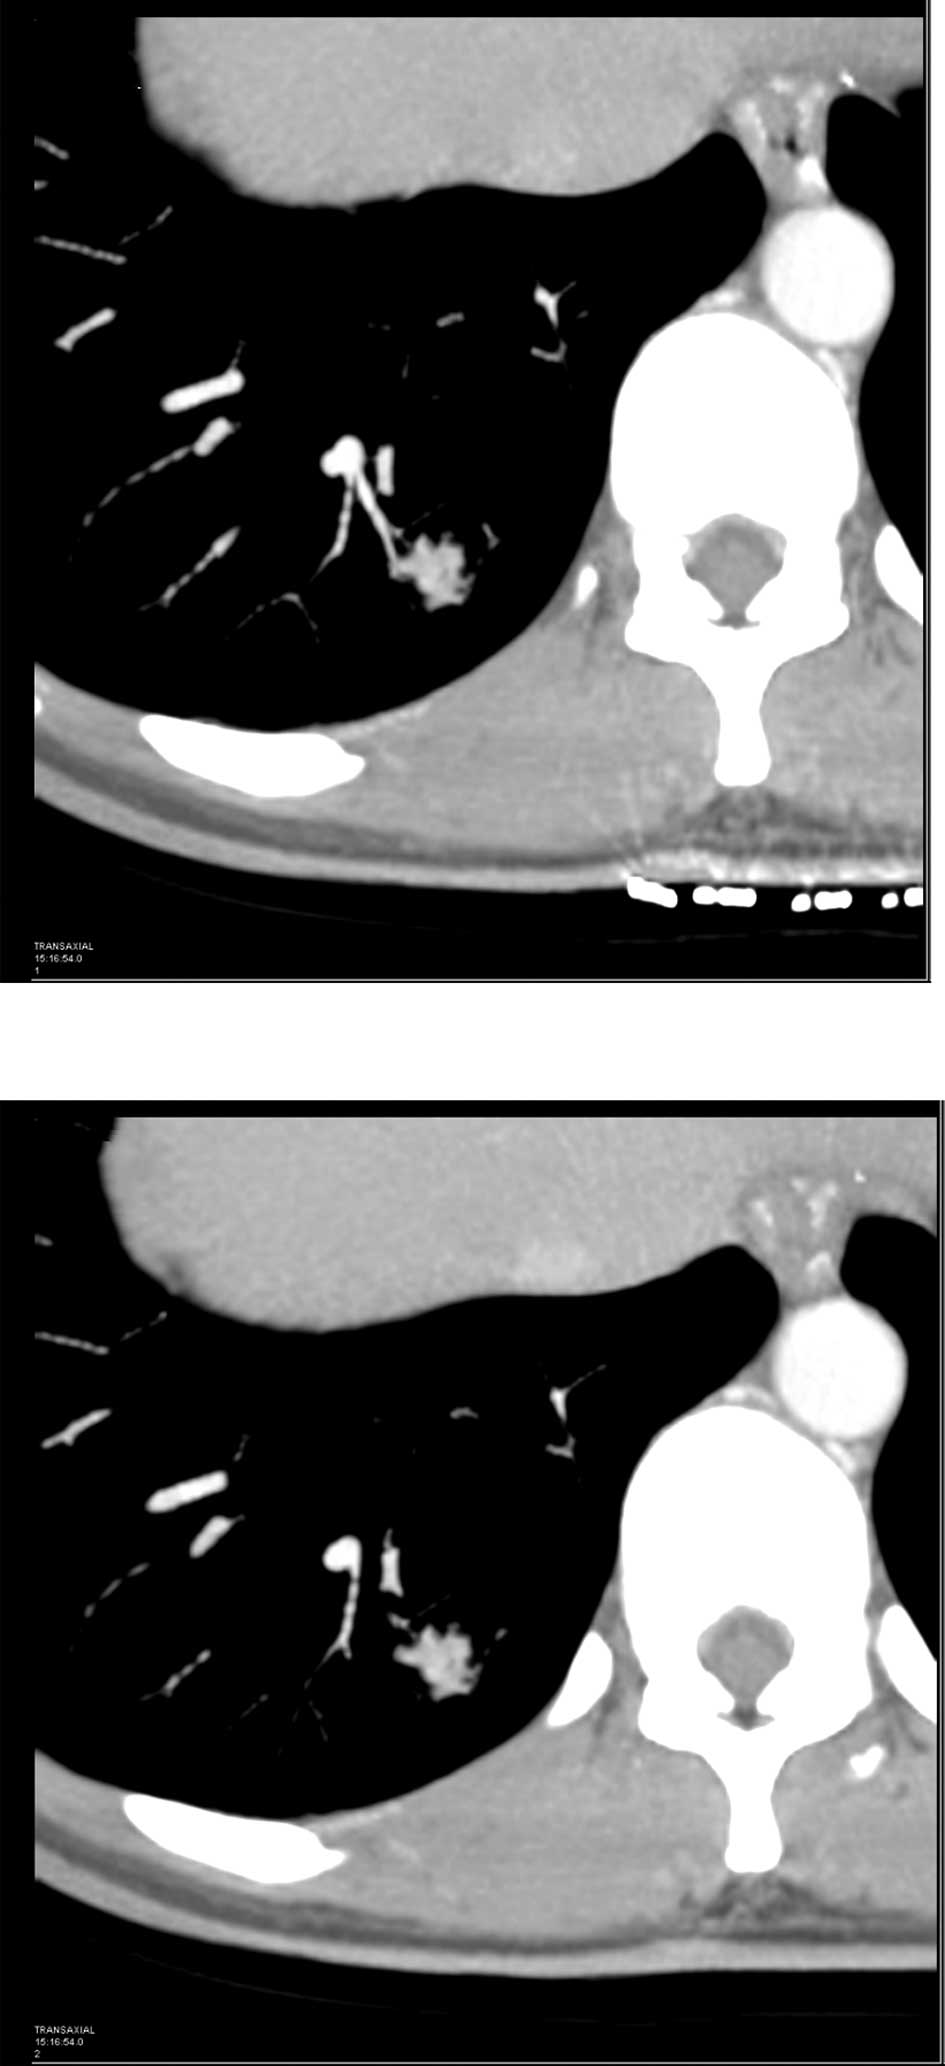

A case of pulmonary sclerosing hemangioma with low 18FDG uptake in PET

Pulmonary sclerosing hemangioma (PSH) is a relatively rare benign neoplasm, often asymptomatic and presenting as a solitary pulmonary nodule on radiological imaging studies. In the present case report, we examined a case of PSH in a young adult female, and reviewed the literature pertaining to PSH with an emphasis on 18F-fluorodeoxyglucose positron emission tomography/computed tomography (18FDG PET/‌CT) and pathology. Immunohistochemical staining was also performed to confirm the diagnosis of sclerosing hemangioma. The results revealed that the tumor cells were immunopositive for epithelial membrane antigen, thyroid transcription factor-1 and vimentin and cytoskeleton 7. The patient recovered and was discharged. Thus, 18FDG PET/CT may be used in the diagnosis of a solitary benign pulmonary nodule.

Figure 1

Figure 2

Figure 3

Figure 4